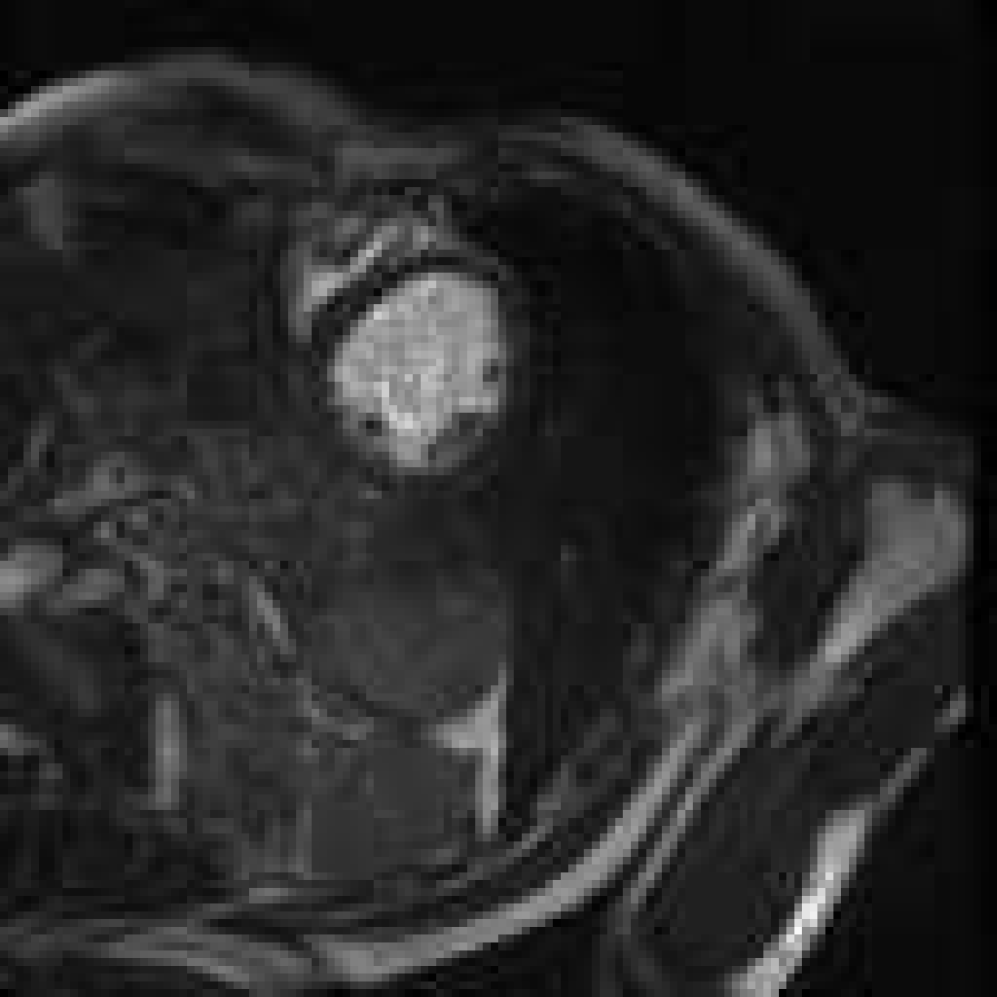

Figure 4: Image synthesis using various τ\tau and diffusion range NN with fixed D=4D=4. Since τ\tau controls the step size of guidance, a very small τ\tau results in no guidance.

Figure 5: Controlling structural consistency by extremal settings of DD and τ\tau. All images are synthesised using the same reference (indicated with a yellow arrow in Fig.  4). From left to right: (D=16D=16, τ=1\tau=1), (D=32D=32, τ=1\tau=1), (D=1D=1, τ=18\tau=18), and (D=1D=1, τ=24\tau=24). Large DD induces semantic drift; high τ\tau leads to more preservation of the reference anatomy.

Synthetic cardiac MR images (Fig. 4 and Fig. 4) closely resembled their respective reference image with good reconstruction on the three important regions of interest (LV, RV, MYO). With different refinement scale for image adaptation, the cardiac MR images had different level of reconstruction, highlighting a controllable trade-off between introducing novel synthetic structures and preserving reference anatomy (Fig. 5). Visual assessment revealed occasional white artifacts in the background of the generated images, likely caused by residual noise retained during the reverse process. Nevertheless, the overall anatomical structures remained well-preserved, even in the presence of a limited dataset. While diffusion models are traditionally considered data-hungry, our results suggest that structural fidelity can be maintained with constrained data availability.